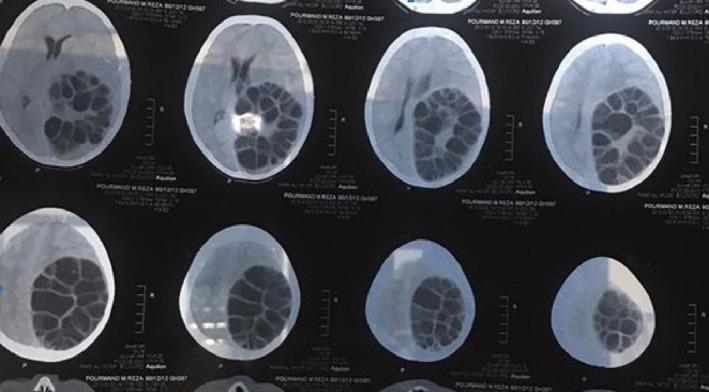

The diagnosis of hydatid cyst should be considered in children with seizure in endemic regions.

在流行地区,癫痫发作的儿童应考虑包虫囊肿的诊断。